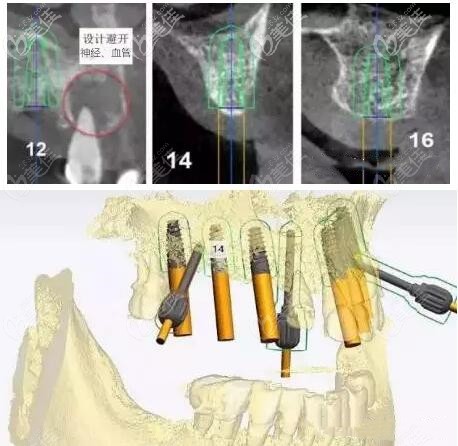

種植牙方案:即刻負重——由于上頜的牙槽骨條件較差,并且有較多的拔牙窩。所以,做即拔即種、即刻修復(fù)種植牙;利用3D數(shù)字化導(dǎo)板技術(shù),避開牙神經(jīng)、血管,找到合適的種植位點。

這樣種植初期的穩(wěn)定性才能更好,并實現(xiàn)即刻負重的效果。

拔除殘牙→安裝3D數(shù)字化種植牙導(dǎo)板→對照3D導(dǎo)板在牙槽骨上植入種植體→完成種植手術(shù)→戴臨時牙冠。